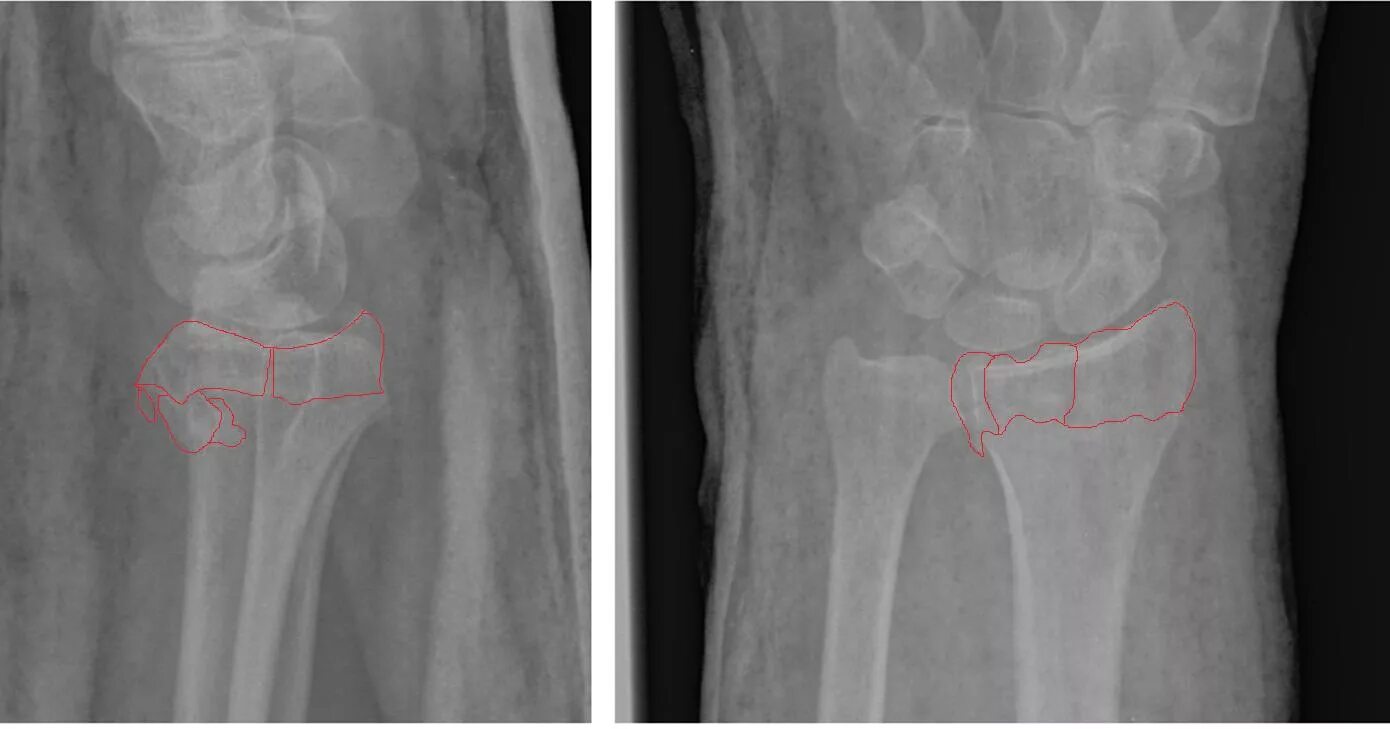

Мкб перелом луча в типичном